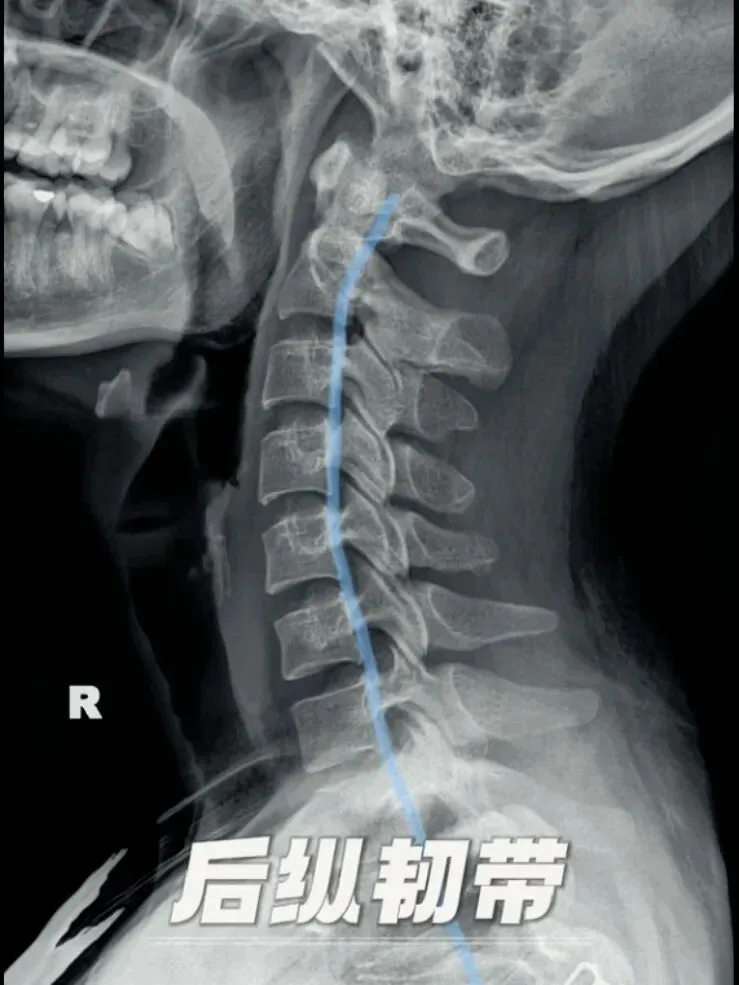

再其次是后纵韧带,位于椎管内椎体的后面,窄而坚韧,起自枢椎,并与覆盖枢椎椎体的覆膜相续下达骶骨,有限制脊柱过度前屈的作用。

当这条韧带因为未知的原因悄然钙化增厚,最终异化成坚硬的骨铠甲时,他便从保护者转变为潜在的压迫者。

这便是颈椎后纵韧带骨化特征,是颈椎后纵韧带组织被异位骨组织替代,形成沿椎体后缘分布的条索状或斑块状骨化灶,这些骨化灶如同在椎管内壁生长的肿物,逐渐侵占空间,压迫脊髓与神经根,常与弥漫性特发性骨肥厚共同存在。